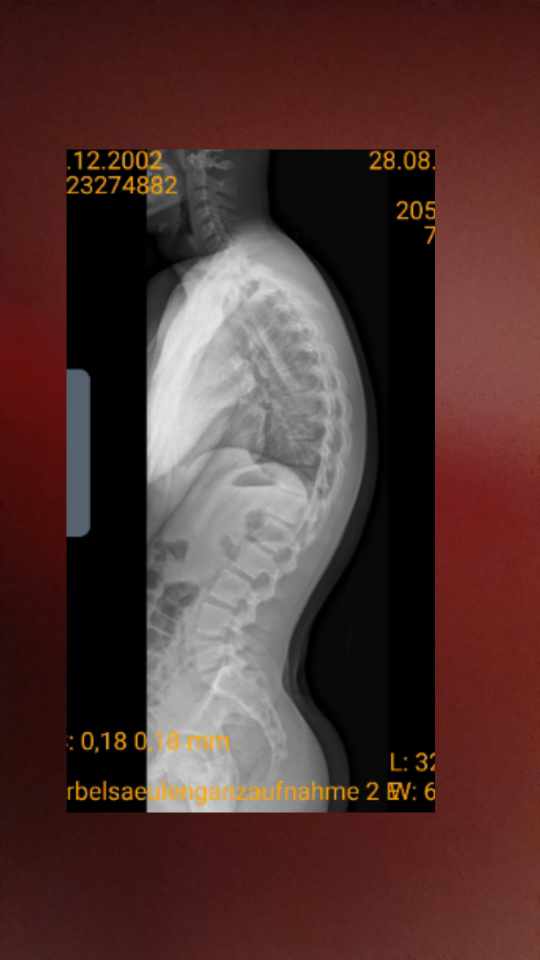

Man sieht klar das der oberschenkelhals also die schwarze Linie mit pt, pelvic tilt die lws schneidet. Bei mir liegt sie auf jeden Fall davor und schneidet sie nd erst ganz oben c1 vllt. C7 und l3 sind aber im lot. Ich hab das bei vergleichen mit anderen röntgenbildern nie gefunden ausser es lag ein flachrücken vor aber beim rundrücken oder hohlkreuz oder beides nie. Könnte das das Problem sein für meine Schmerzen und das ich immer das gefühl habe nicht im lot zu sein Gleichgewicht zu haben. Ich würde mich sehr über Antworten freuen. Schonmal danke im vorraus

Für mich, als Laien, sieht es nach einer Hyperkyphose und einem Hohlkreuz aus.

Das deckt sich mit dem Röntgenbild und in der Regel ergibt sich in so einer Situation auch ein "anterior pelvic tilt" und mit dem Rundrücken ein Ausgleich, um im Lot zu stehen.Undzwar sieht es bei mir optisch so aus als hätte ich ein hohlkreuz und ein rundrücken

Ich habe eine neues Thema eröffnet, weil ich dachte das es mir bei diesem Anliegen um was anderes geht als beim mal davor. Die Skizze die ich reingeschickt habe ist aus einem Beitrag von der sagittalen Balance der wirbelsäule und welche Rolle sie spielt bei Behandlungen konservativ und operativ. Jeder rücken ist ja anders was die Beschwerden betrifft und was der Auslöser ist und meiner nach kann man so gut rausfinden, woran es liegen könnte. Also halt an den Krümmungen lordose kyphose etc aber halt auch wie die sagitalle Balance ist. Und hat dieser Skizze und andere Skizzen zu dem Thema sieht man bei mir zwar c7 und l3 auf einer Höhe sind aber man sieht auch, dass mein oberschenkelhals (linie pt) zu weit vorne ist. Bei einem anterior pelvic bzw hohlkreuz tilt ist er aber tendenziell zu weit hinten. Und wenn ich mein röntgenbild mit anderen online vergleiche die scheuermann typ 1 haben sieht man bei jedem das diese Linie die unteren lendenwirbel schneidet. Daher ist meine Meinung, dass mein Becken nach hinten gekippt ist und nicht nach vorne auch wenn es optisch so erscheinen mag. Ich weis, wie du schon sagtest am besten sollte icj das mit einem Spezialisten abklären lassen, das werde ich auch bald machen, ich wollte halt eine Diskussions Runde starten, weil hier der ein oder andere mit weit mehr Erfahrungen auf dem Gebiet rückenerkrankungen fehlstellungen etc ist und Tipps erhalten oder Meinungen austauschen ob sowas möglich ist etc.

Ich war jz in groshadern lmu klinikum münchen und habe das alles vermessen lassen. Das komische vei mir ist das in einem normalen scheuermann die bws versteift ist meist und die lws dies versucht auszugleichen durch mehr lordose und arbeit. Bei mir ist aber due bws ohne einschränkungen zumindest laut dem ott test bei der lws kommt allerdings beim schober test 10 12 alsi statt der gwünschten +5cm nur 2cm das macht die situation zu eienr ganz anderen ausserdem steht mein hüftgelenkszzentrum ca 4cm smzu weit vorne also die pt linie schneidet in der sagitalen ebene kein einzigen lendenwirbel gleichzeitig stehen c7 und s1 im lot. Das die pt so weot vor der lws liegt öiegt daran das ich als kompensation der steifen lws die zz rund ist von anfang am das becken sehr nach vorne schieben muss um das auszugleichen also das becken ist seht weot vorne die lordose aber nixht merh. Ausserdem ist meine kyphose von 58 grad bei nur 50 lordose zu viel für die sagitale balance. Mein pi mit 55 passt zwar zur lordose aber insg für die kyphose ist es zu wenig. Aber das komuschste ist das ich noch nie einen scheuermann typ 1 rundrücken gefunden habe wo die pt linie nicht die lwndenwirbel schneidet obwohl das der anker für alles ist bei gleichzeitiger lws verstoefung und mobiler bws. Eigenrlich kommt so etwas bei eienm flachrpcken vor wenb alles zu flach ist weil das surch die fehlende lordose ser pt sagital nicht durch die lendenwirbel gehn kann

Die sagittale Balance ist bei den beiden angegebenen Winkeln natürlich nicht gegeben. Im Röntgenbild sehe ich als Ausgleich eine steilgestellte HWS (verminderte HWS Lordose).Ich war jz in groshadern lmu klinikum münchen und habe das alles vermessen lassen......Ausserdem ist meine kyphose von 58 grad bei nur 50 lordose zu viel für die sagitale balance.